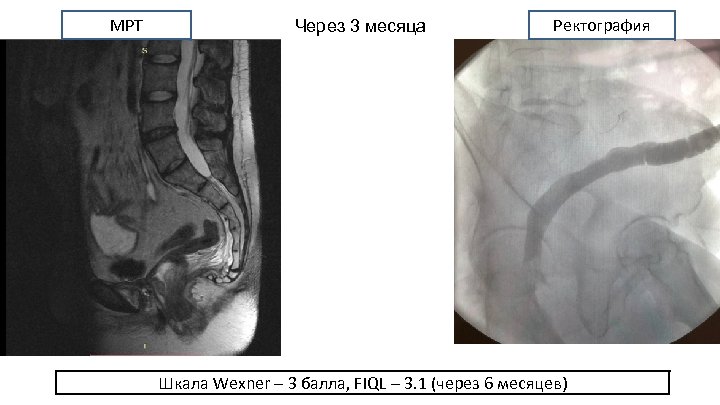

МРТ Через 3 месяца Ректография Шкала Wexner – 3 балла, FIQL – 3. 1 (через 6 месяцев)